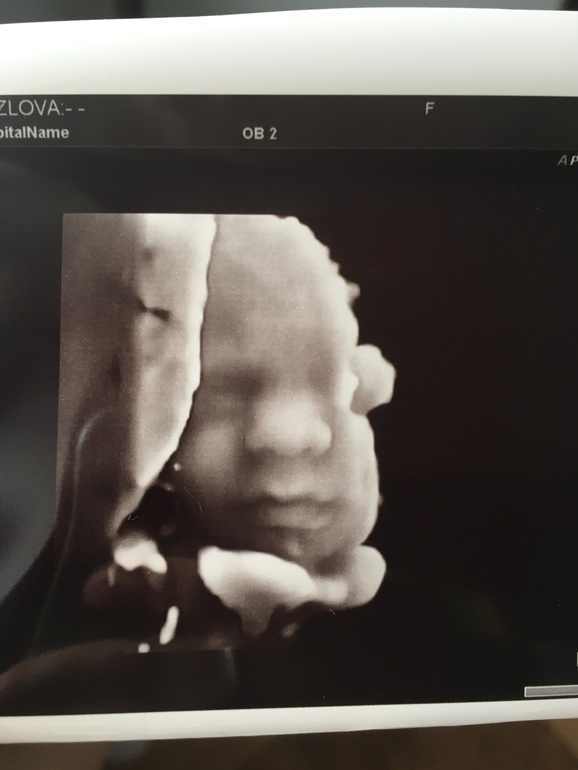

Я улеглась на кушетку, врач пару секунд поводила датчиком по животу и сразу повернула ко мне монитор, а там ... сладкие щечки и пухлые губки

Попозировал мне немного и потом прикрылся ручкой

Короче, Мам , отстань))

Малыш уже такой большой и сладкий